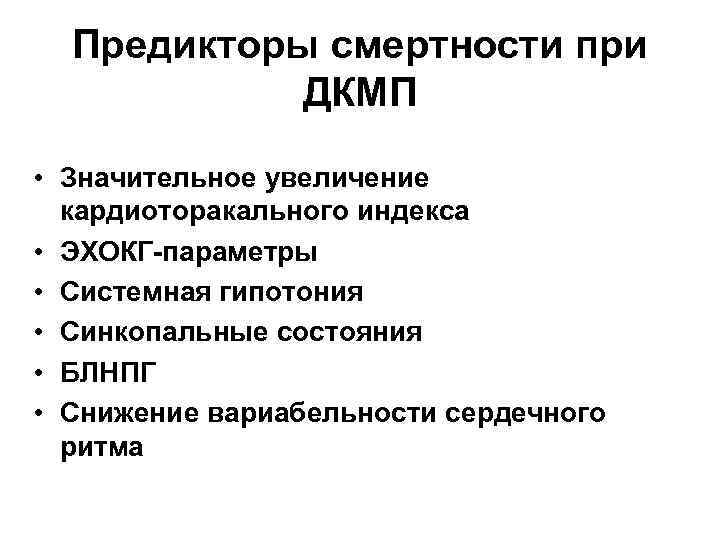

Предикторы смертности при ДКМП • Значительное увеличение кардиоторакального индекса • ЭХОКГ-параметры • Системная гипотония • Синкопальные состояния • БЛНПГ • Снижение вариабельности сердечного ритма

Предикторы смертности при ДКМП • Значительное увеличение кардиоторакального индекса • ЭХОКГ-параметры • Системная гипотония • Синкопальные состояния • БЛНПГ • Снижение вариабельности сердечного ритма